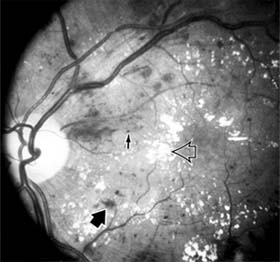

The fragile new vessels proliferate onto the posterior face of the vitreous and become elevated once the vitreous starts to contract away from the retina. If the vessels bleed (Figure 10-26), massive vitreous hemorrhage may cause sudden visual loss. Eyes in which posterior vitreous detachment is complete are at less risk of developing neovascularization and vitreous hemorrhage. In eyes with proliferative diabetic retinopathy and persistent vitreoretinal adhesions, elevated neovascular fronds may undergo fibrous change and form tight fibrovascular bands that tug on the retina and exert continued vitreous contraction. This can cause either a progressive traction retinal detachment or, if a retinal tear is produced, rhegmatogenous retinal detachment. The retinal detachment may be heralded or concealed by vitreous hemorrhage. When vitreous contraction is complete in these eyes, proliferative retinopathy tends to enter the burned-out or "involutional" stage.

Figure 10-26

Figure 10-26: Proliferative diabetic retinopathy with preretinal hemorrhage obscuring the inferior macula. Macular exudate, microaneurysms, and intraretinal hemorrhages are also present.